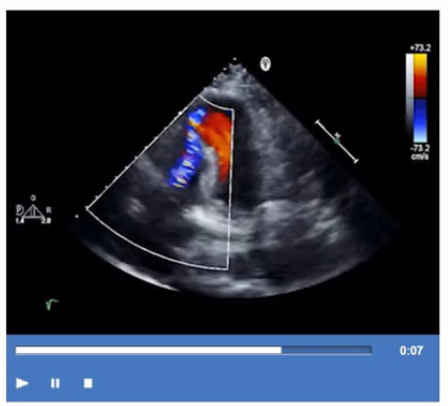

Which type of defect can be seen in this video clip?

The echocardiographic video shows a defect in the ventricular septum with left-to-right shunting consistent with an ischemic ventricular septal defect (VSD), a mechanical complication of myocardial infarction. The defect allows blood flow between the left and right ventricles.

Coronary artery aneurysm appears as dilated coronary vessels, not a septal defect. Tricuspid regurgitation involves the right atrioventricular valve and is identified differently. Pseudoaneurysm of the apex is a contained myocardial rupture with narrow neck and does not involve septal communication.